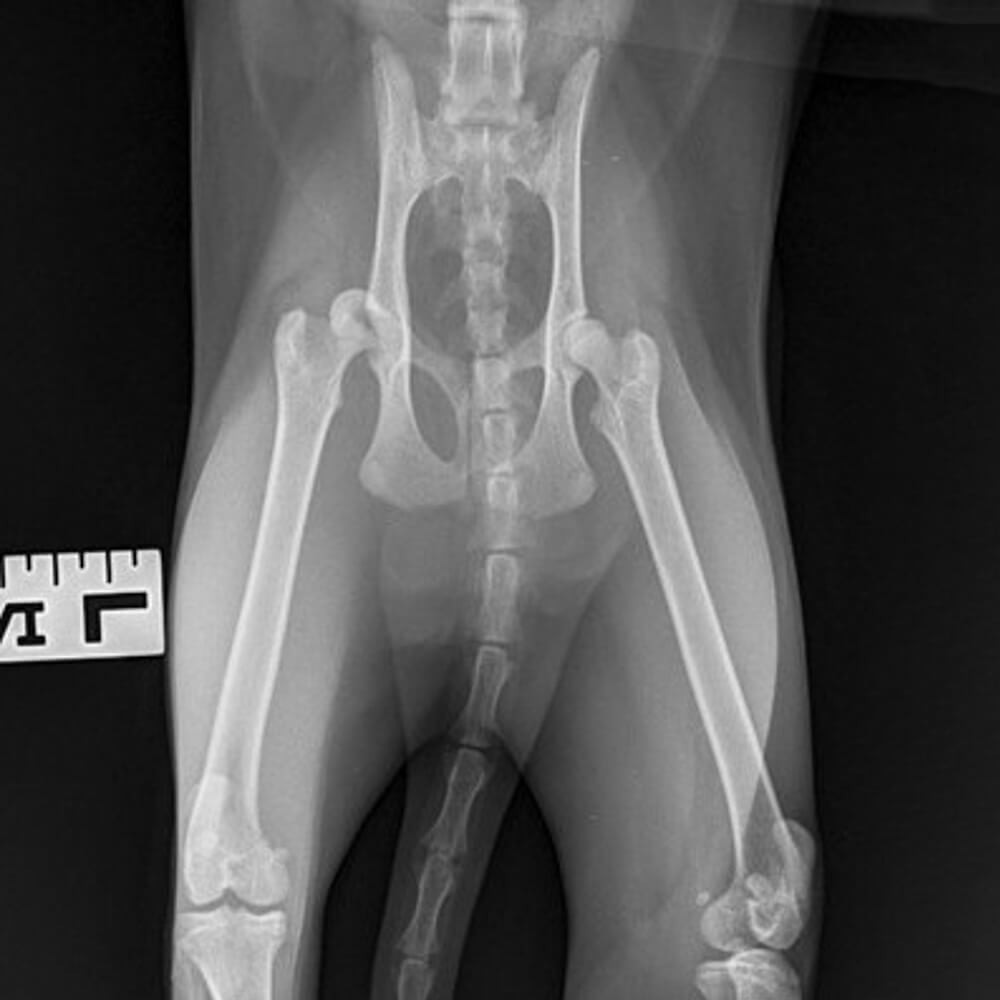

Salt came to us after, on returning home from her daily adventures, her owner noticed she was not placing weight through one of her hind limbs.

Salt was admitted for x-rays where it was found she had dislocated her hip. There were no fractures to the pelvis or hindleg. This had probably been caused by a fall and Salt would require surgery to alleviate her pain.

There are a number of surgical corrections available for this type of injury. Salt had a femoral head and neck excision. This removes the femoral head, alleviating the pain from bone on bone contact, and creates a joint made up of dense fibrous tissues. After a period of time Salt made a full recovery and is back to enjoying her daily adventures!